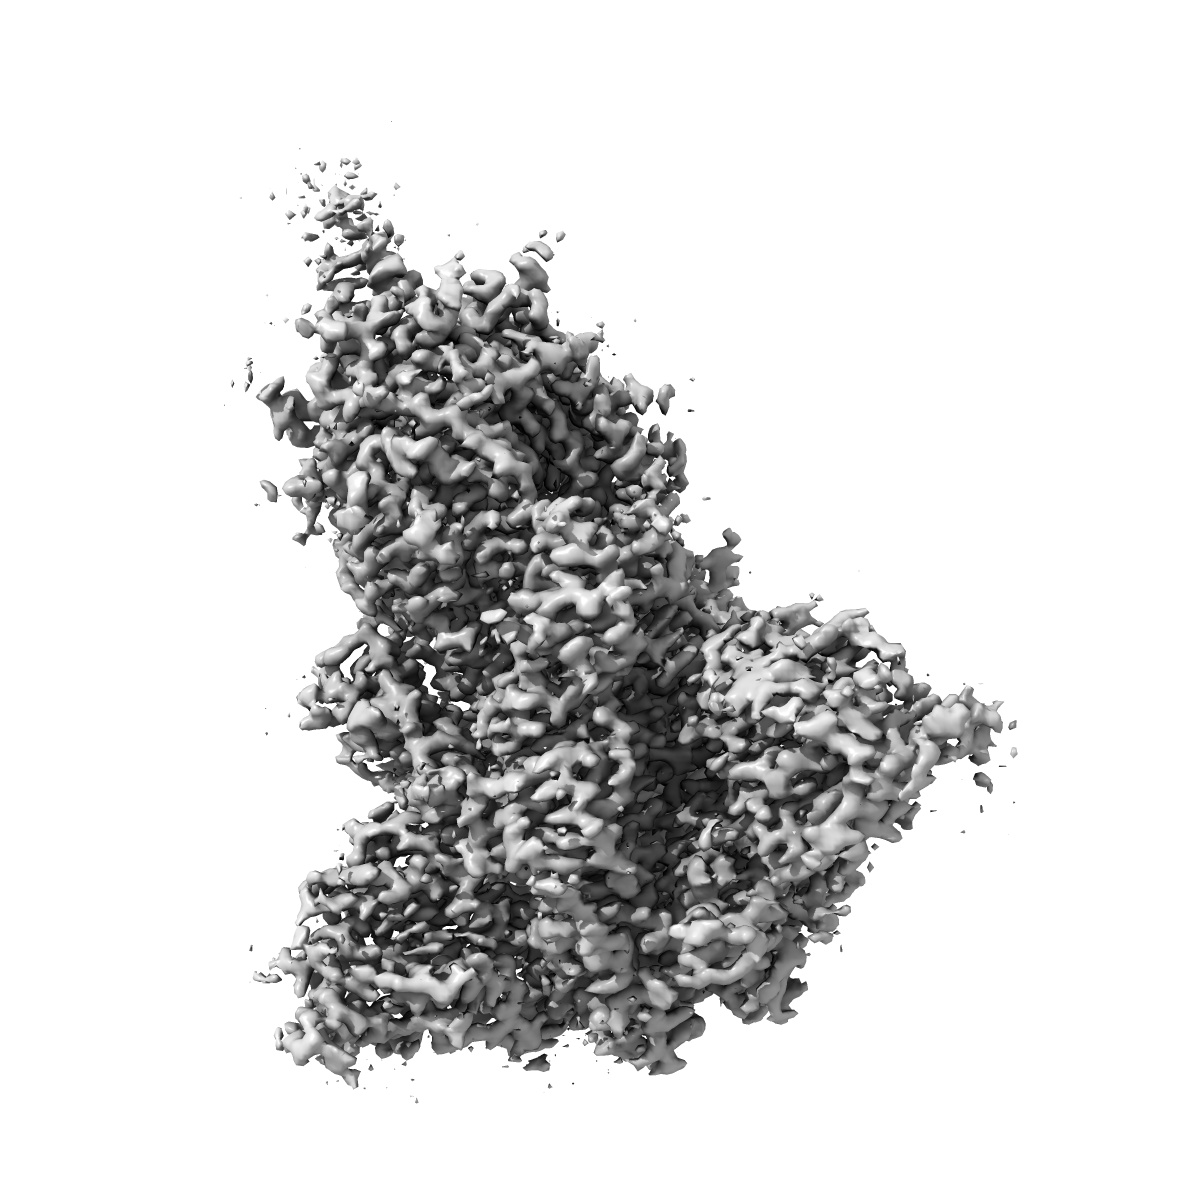

S protein of SARS-CoV-2 in the locked conformation

EMD-30889

Single-particle

2.7 Å

Sample: S protein of SARS-CoV-2 in the locked conformation

Fitted models: 7dwy

Structural basis for the different states of the spike protein of SARS-CoV-2 in complex with ACE2.

Yan R, Zhang Y, Li Y , Ye F , Guo Y , Xia L, Zhong X, Chi X, Zhou Q

(2021) Cell Res , 31 , 717 - 719